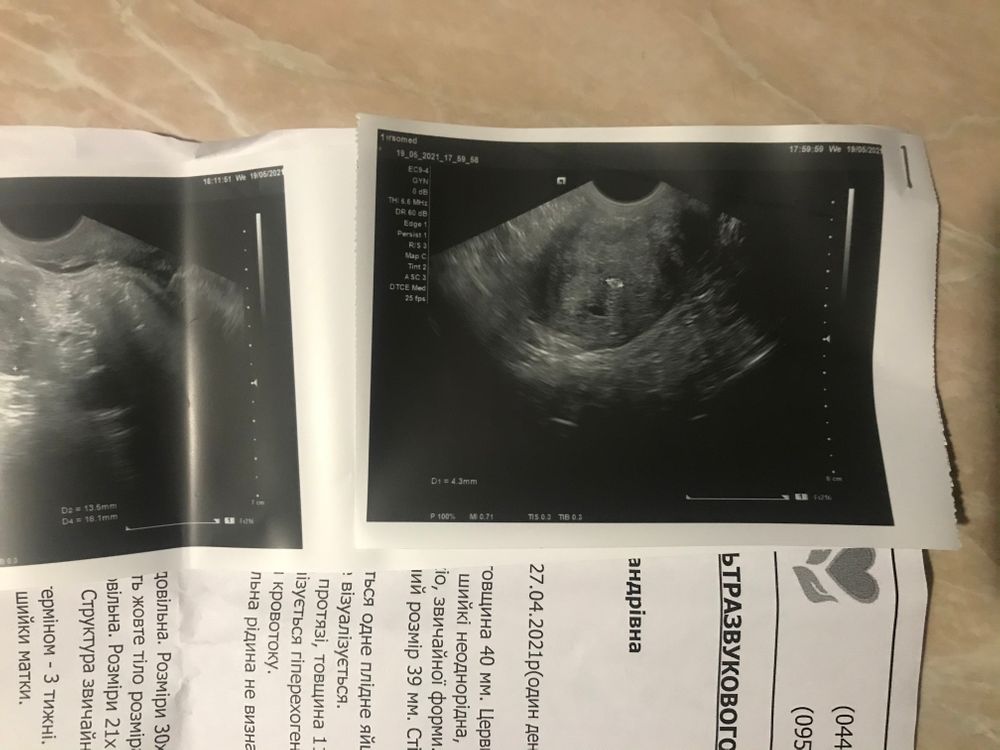

На узи плодное яйцо - как врач говорит

11.05 - 3 мм (гос Клиника )последнее фото

19.05 -5.6 мм ( частная клиника )первое

Что это может быть , аденомиоз может ?

Yana, была на ещё одном узи , это образование присутствует

Аденомиоз мне кажется не может быть одной точечной локализации, мне ставили такой диагноз по УЗИ, но делали на 3Д и там как то эти участки закрашивались и было понятно

Повторите через неделю но сделайте на хорошем аппарате чтобы точно, ПЯ при отрицательном ХГЧ в крови я думаю не бывает